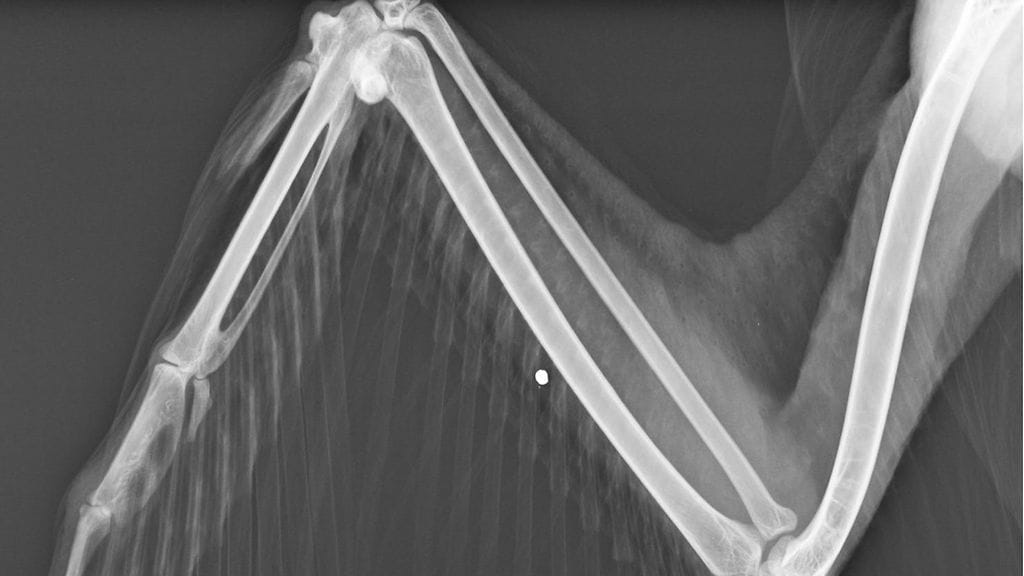

Kanadanhanhi nukutettiin tänään ja tutkittiin tarkemmin. Korkeasaaren mukaan röntgenkuvissa näkyi hauleja siivissä ja rintaontelossa.

– Kipulääkkeistä huolimatta siivet roikkuivat ilmeisesti hermovaurioiden tai hauleista ja vääntämisestä hajonneiden nivelsiteiden vuoksi.